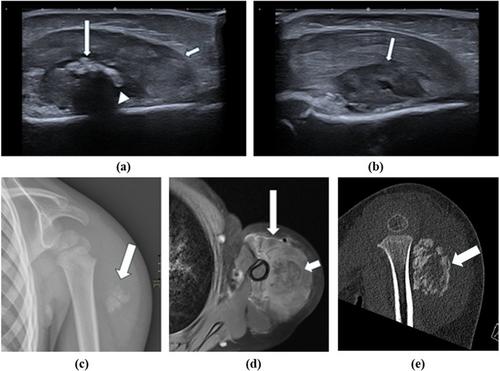

Myositis ossificans (MO) is a benign soft tissue lesion, characterized by ectopic ossification due to inappropriate fibroblast differentiation, most commonly affecting skeletal muscles. It often occurs in young adults after muscle trauma, predominantly in male patients and very rarely in children. We describe the case of a previously healthy 3-year-old boy who developed a lesion in his deltoid muscle after vaccination against tick-borne encephalitis. During an MRI scan, performed under general anesthesia, fine needle aspiration biopsy (FNAB) and core needle biopsy (CNB) were performed. While the CNB sample resulted in a non-diagnostic finding, the FNAB sample showed cytomorphology consistent with the diagnosis of MO. A molecular analysis performed on the FNAB sample confirmed the presence of COL1A1::USP6 fusion, which is considered diagnostic for MO in the appropriate clinical context. The boy was then referred to the orthopedic surgeon. Extracorporeal shock-wave therapy was chosen as the first-line treatment, but as it was too painful, the lesion was surgically removed, and histopathologic evaluation confirmed the diagnosis. Although rare in children, the diagnosis of MO should be considered in soft tissue lesions after trauma. We present the first pediatric case of MO diagnosed by FNAB and propose that FNAB, as a minimally invasive diagnostic procedure, is a suitable diagnostic approach, especially when molecular testing is available to confirm the diagnosis.